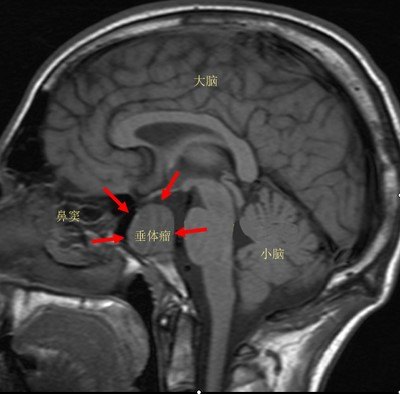

垂体正常及常见疾病影像表现

人的脑垂体在哪里

脑垂体

神经系统和内分泌系统的中心-下丘脑脑垂体是人体最重要的内分泌腺,是